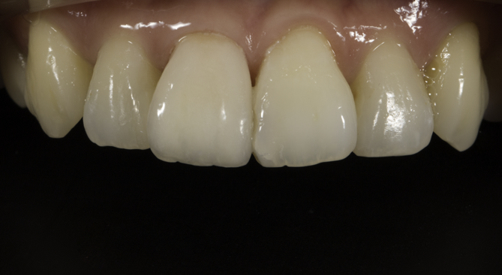

Minimal Prep Veneers to correct a discoloured tooth and improve form

4 Platinum Foil Veneers